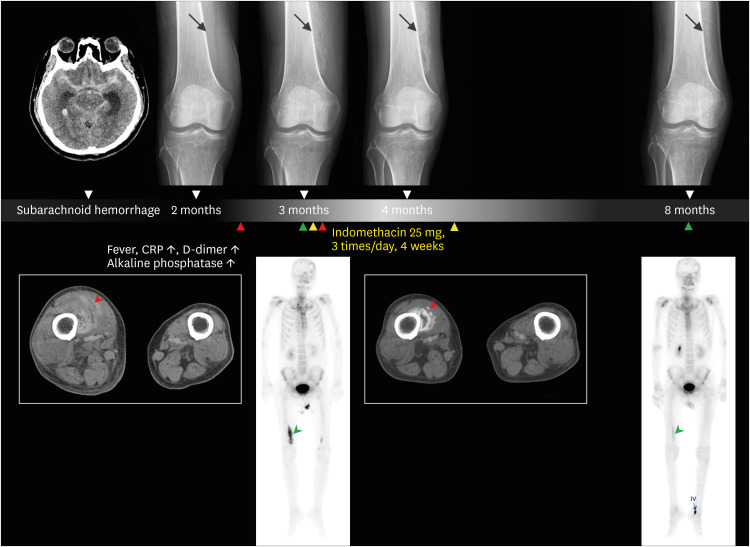

Myositis ossificans is uncommon in patients with nontraumatic brain injuries. This report presents a challenging case in which myositis ossificans was diagnosed and treated by medical management in a patient who was unable to complain of any symptoms due to akinetic mutism that occurred after nontraumatic subarachnoid hemorrhage. The patient had intermittent high-grade fever, and laboratory tests showed elevated C-reactive protein and D-dimer levels without clinical signs of infection two months after subarachnoid hemorrhage. Lower-extremity venography using computed tomography was performed to rule out deep venous thrombosis. There was no thrombus, but right vastus medialis muscle showed inflammatory change with faint multilayered curvilinear hyperdense rims. The administration of indomethacin helped prevent abnormal bone formation. For the early detection of myositis ossificans, careful observation of clinical presentation and a high index of clinical suspicion is necessary in brain-injured patients. Further, elevated serum inflammatory markers accompanied by elevated alkaline phosphatase can be a critical clue. Early computed tomography helps identify early 'string sign' prior to characteristic ossification. Our report highlights that the myositis ossificans is remediable by early detection and appropriate nonsurgical management.